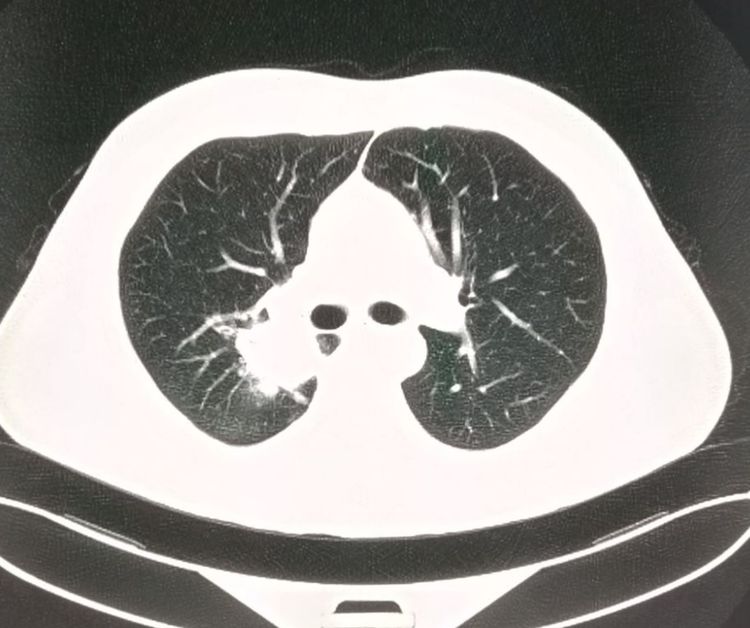

我们先看一个浸润性肺腺癌的病人,老年男性,咳嗽、胸背疼来医院就诊。

胸部CT发现右肺门旁的肿块,有分叶,有胸膜牵拉:

看过豪大夫肺结节系列文章的读者朋友可能就会判断出,这个肿瘤不是早期了!手术切除有复发风险,还需要配合后续治疗。